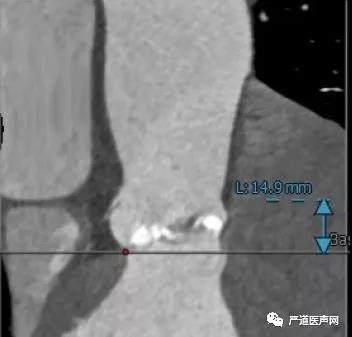

术前CT:

左冠开口高度14.9mm